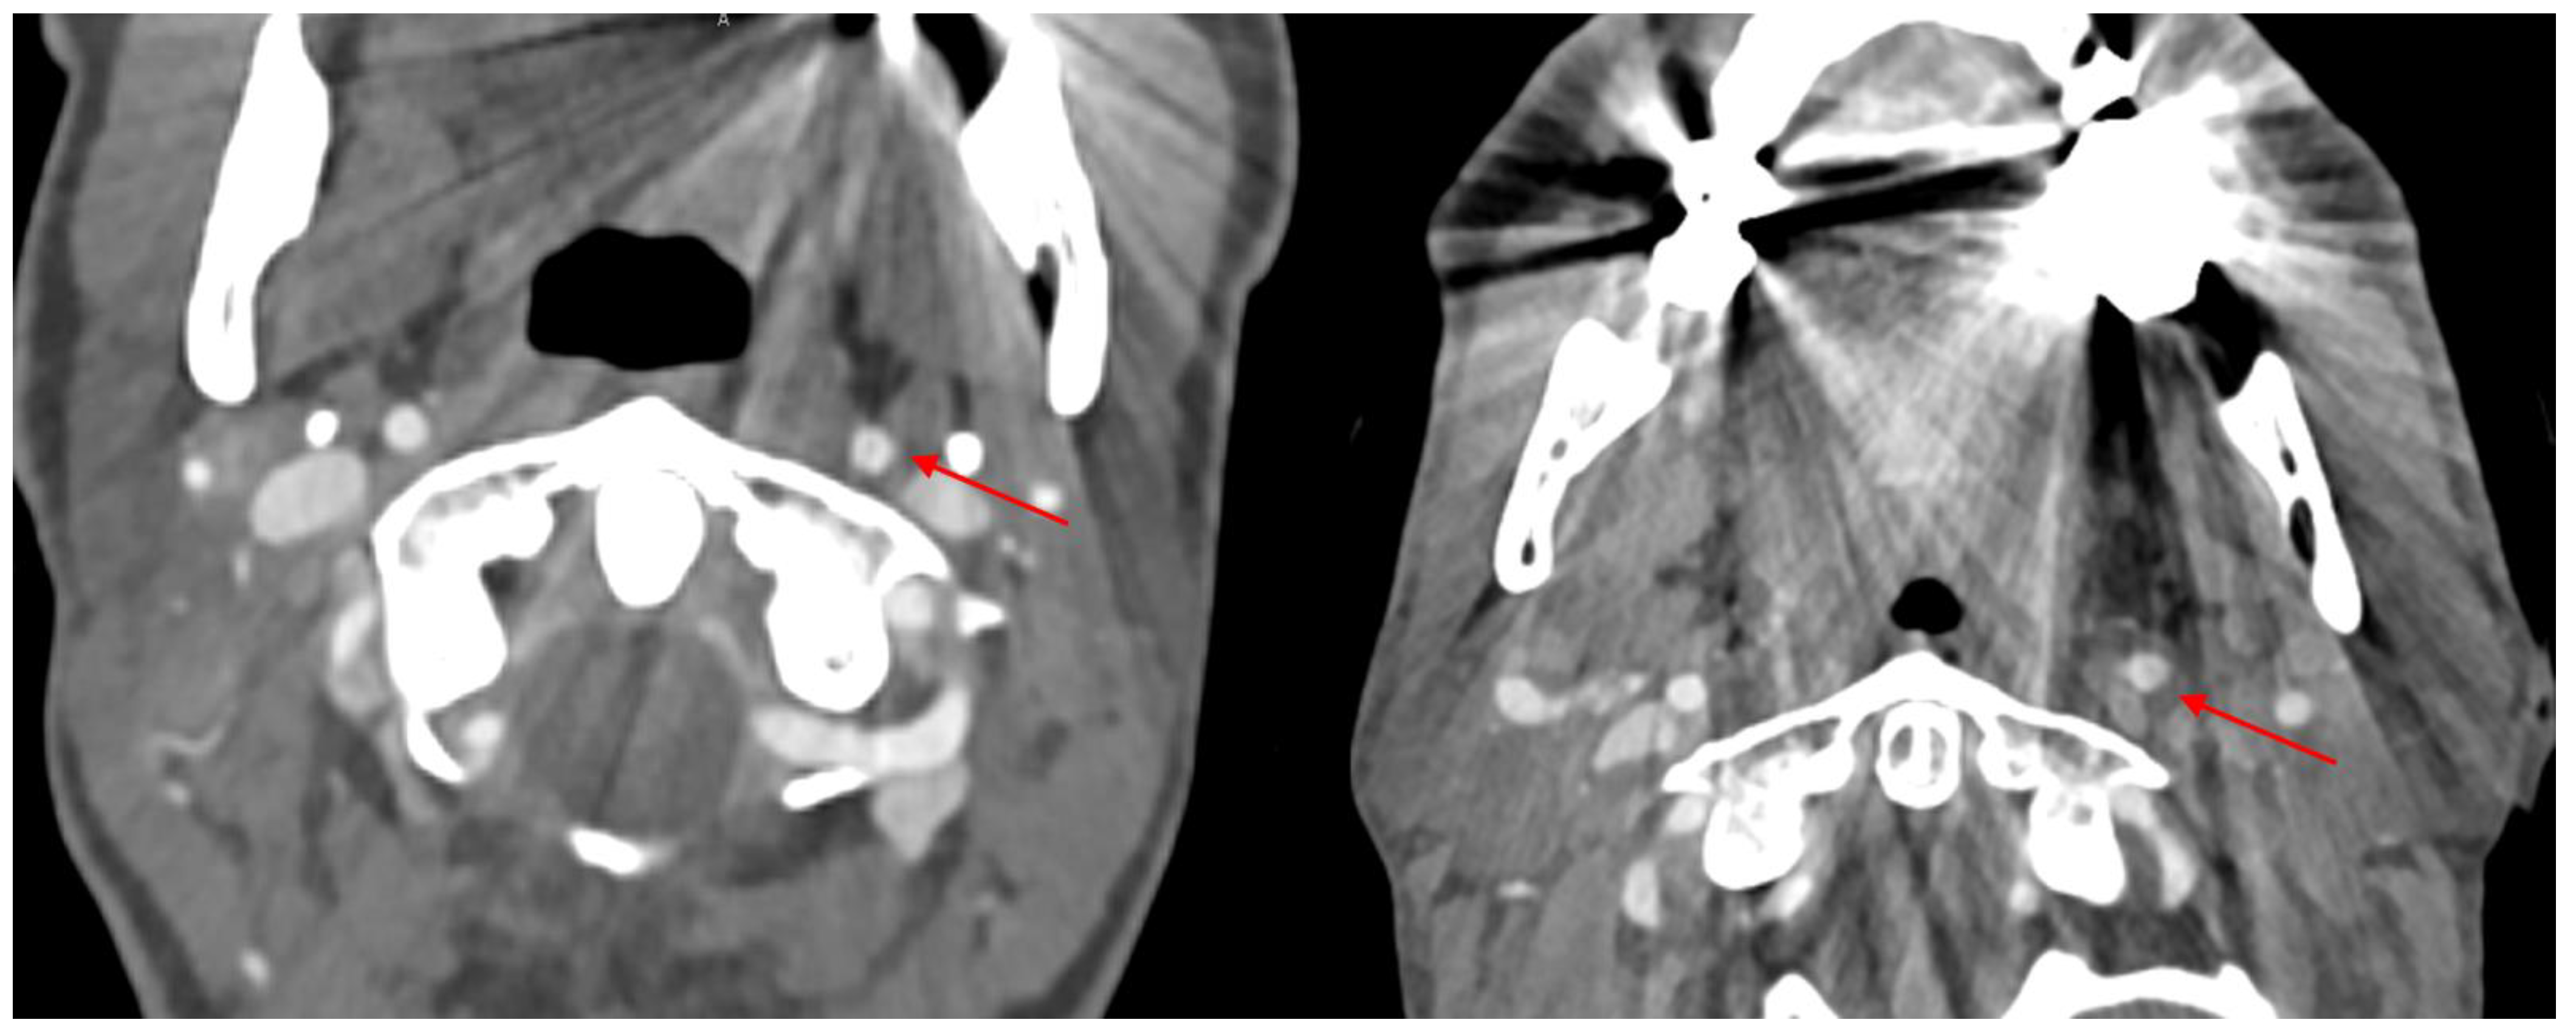

3.2. Hyperattenuation Artifacts

3.3. Hypoattenuation Artifacts